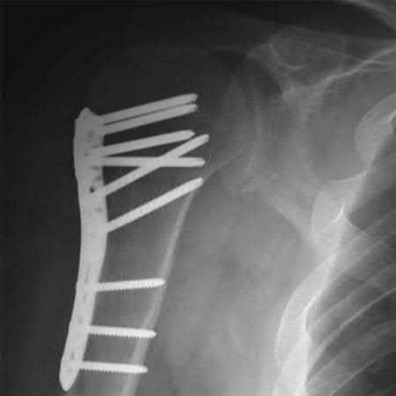

A 64-year-old woman is thrown off a horse, sustaining the injury shown in Figures A and B. She undergoes surgical fixation as seen in Figures C through E. What is the most commonly reported complication of this procedure?

1) Axillary nerve injury

The patient in the scenario has a 2-part proximal humerus fracture treated with a locking plate as seen in Figures A-E. The most common complication with the use of this implant is screw penetration. The terms screw cut out and penetration are often used interchangeably in the literature with cut out appearing more frequently in reports regarding intertrochanteric fractures.

Owsley et al retrospectively reviewed 53 proximal humerus fractures treated with locking plates and the same post-operative protocol. The most common complication was screw cut out or penetration, followed by varus displacement. They concluded that 3 and 4-part fractures in patients over 60 years have a higher incidence of failure.

Agudelo et al retrospectively reviewed 153 patients at a level-one trauma center treated with proximal humerus locking plates, investigating modes of failure for the implant. They determined that varus malreduction (head-shaft angle